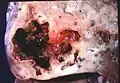

L'abcès pulmonaire est un type de nécrose liquéfiée du tissu pulmonaire et la formation de cavités (plus de cm)[1] contenant des débris nécrotiques ou du liquide, causée par une infection microbienne.

Les abcès pulmonaires sont souvent d'un seul côté et concernent les segments postérieurs des lobes supérieurs et les segments apicaux des lobes inférieurs, car ces zones dépendent de la gravité en position couchée. La présence de niveaux air-fluide implique une rupture dans l'arbre bronchique ou, rarement, la croissance d'un organisme gazogène.[réf. nécessaire]